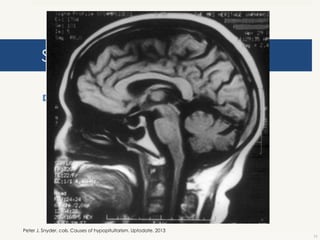

Síndrome de silla turca vacía

 Congénita o adquirida después de cirugía.